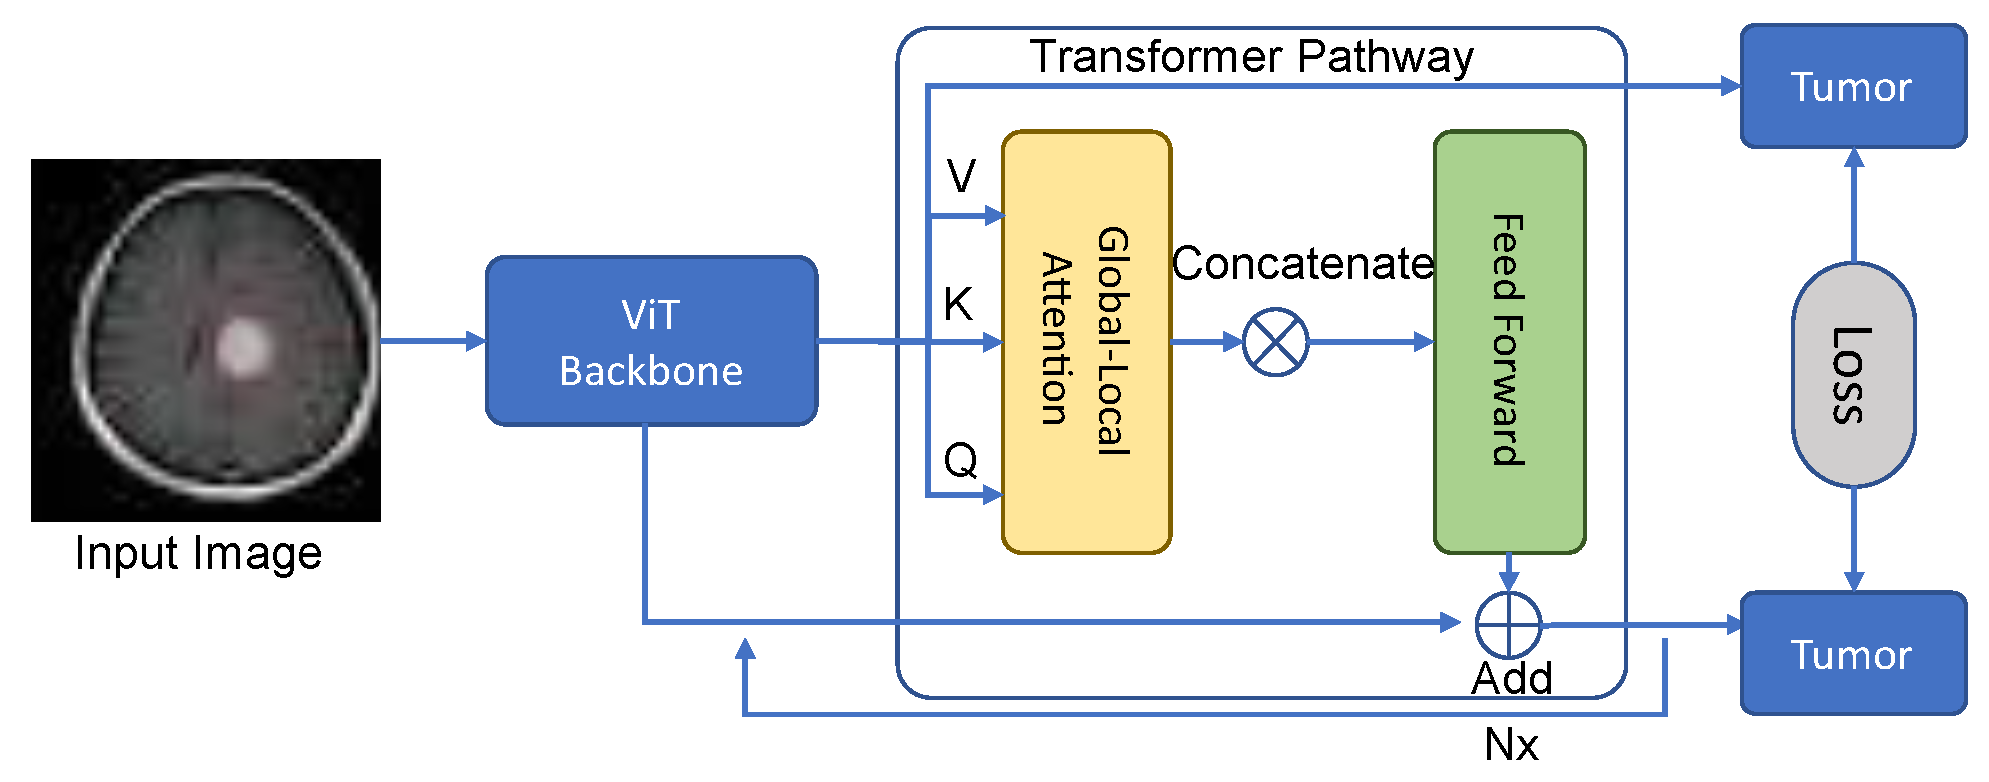

3.2. Transformer Pathway